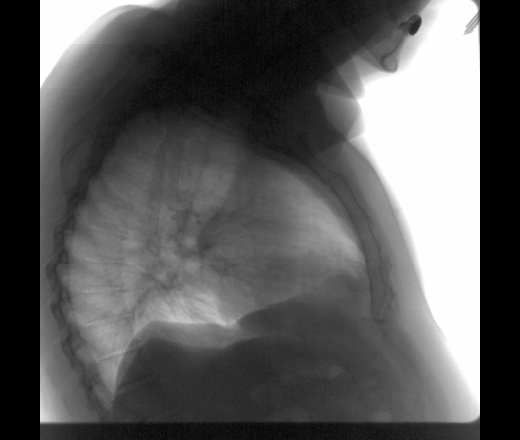

Что такое осумкованный междолевой плеврит на КТ?